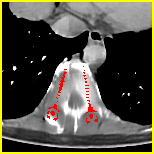

Effect of metal mask projection (SE0-Net vs SE-Net). From Table 1, we can observe the use of instead of improves the performance for at least 4.1 dB in PNSR and reduces MSE from 0.95219 to 0.00074 for all metal sizes. The groups with large metal implants benefit more than groups with small metal implants. As shown in Fig. 4, the artifacts in metal trace of SE0-Net are over-removed or under-removed, which introduces bright and dark bands in the reconstructed CT image. With the help of , SE-Net can suppress the artifacts even when the metallic implants are large and the surrogate data are more consistent with the correct data outside the metal trace.

Effect of sinogram padding (SE-Net vs SEp-Net). Sinogram padding mainly improves the performance in the group with the largest metal objects, with a PSNR gain of 0.15 dB and an MSE reduction of 0.00048. As shown in Fig. 4, the model with sinogram padding restores finer details of soft tissue between large metallic objects because more correct information is retained by periodic padding than zero-padding.

Effect of learning with (SEp-IE-Net vs Ours). When is jointly restored with the corrupted , the sinogram correction performance is affected with an increment of 0.00033 in MSE and of 0.7 dB in PSNR. More details of soft tissue around metal are retained and the image becomes sharper, as shown in Fig. 4.